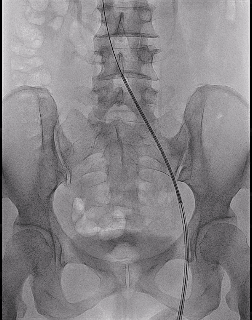

3、扩张结束后,送入Venovo髂股静脉支架 14*120mm,先大滚轮缓慢释放,便于支架近心端的定位,避免过多进入下腔静脉,遮挡对侧髂静脉开口。当近心段充分锚定后,通过小滚轮将整个支架进行完整的释放。